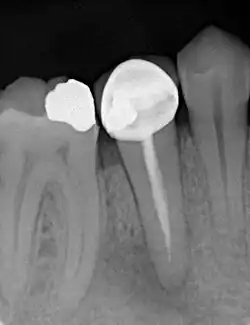

Zur Beurteilung des Erfolges einer Wurzelkanalbehandlung werden klinische Beschwerden, wie Schmerzen, Schwellungen oder Fistelgänge sowie der röntgenologische Befund herangezogen. Oft sind trotz endodontischer Infektion keine klinischen Beschwerden vorhanden, weshalb gerade die röntgenologische Kontrolle Hauptkriterium für die Beurteilung ist.[10] Neben der vorhandenen Wurzelfüllung und Veränderungen in der Wurzelphysiognomie (Resorptionen) wird vor allem der Zustand des periapikalen Gewebes begutachtet und auf das Vorhandensein einer Parodontitis apikalis oder einer radikulären Zyste geprüft.

- Wurzelkanalbehandelte Zähne mit röntgenologisch oder klinisch insuffizienter Wurzelkanalfüllung (z. B. mangelhafte Homogenität der Füllung, nicht behandelte Wurzelkanäle, nicht gefüllte Areale des endodontischen Systems, fragwürdiges und nicht mehr indiziertes Füllmaterial etc.) ohne klinische oder röntgenologische Anzeichen einer Parodontitis apicalis.

Wenn eine Verbesserung des Ausgangszustandes und eine Beseitigung der möglichen Ursachen nicht zu erwarten sind oder die Erhaltung des Zahns fragwürdig ist, ist von einer Revision abzusehen. Ebenso müssen nicht-endodontische Ursachen der Erkrankung vor einem Eingriff ausgeschlossen werden.[1] Nach Strindberg et al. wird der endodontische Misserfolg nach einer ausreichenden Heilungszeit von vier Jahren mit dem Vorhandensein einer residuellen, persistierenden oder progredienten röntgenologischen Aufhellung (Dunkler Punkt an der Wurzelspitze im Röntgenbild) und/oder mit dem Vorhandensein klinischer Beschwerden jeglicher Form definiert.[18]